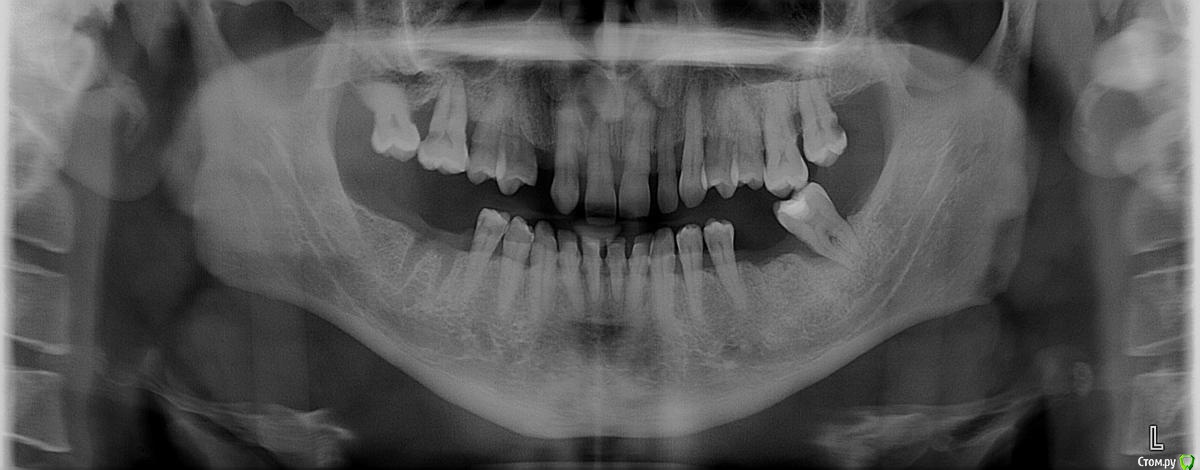

Eleat Опубликовано 6 апреля, 2015 Поделиться Опубликовано 6 апреля, 2015 Здравствуйте! При консультации в стоматологии мне диагностировали парадонтит и рекомендовали следующий план лечения: 1. Вылечить пародонтит.2. Удалить все многокоренные зубы (5 шт)3. Сделать открытый синуслифтинг с двух сторон4. Имплантация жевательных зубов. 8 имплантов по 4 с каждой стороны (2 сверху, 2 снизу)5. В перспективе имплантация передних зубов. так как существующие все разъехались. Мои вопросы:1. Можно ли сделать имплантацию сначала только с правой стороны (аргументы: что бы всегда было чем жевать, растягивание оплаты по времени) или это неразумный подход?2. Удобно ли делать синуслифтинг одновременно с удалением зубов или без разницы. (хотел бы зубы удалить сейчас, а синус-лифтинг сделать после поездки в отпуск)3. Действительно ли нужен открытый синус лифтинг или (судя по фото) может достаточно закрытого?4. Нужно ли сначала лечить парадонтит или лучше после удаления зубов (дешевле в том числе)?5. удобно ли делать одномоментную имплантацию? Извините, если вопросы покажутся глупыми или противоречивыми. Тревожат такие факторы.1. нечем будет жевать2. в мае отпуск, а после синуслифтинга месяц нельзя летать.3. болит зуб 16. я бы его уже удалил, но вдруг надо сразу синуслифтинг делать и еще он упирается корнями в пазуху.4. оптимальный ли план придуман в стоматологии? Что бы вы порекомендовали? Заранее большое спасибо за ответы. Ссылка на комментарий